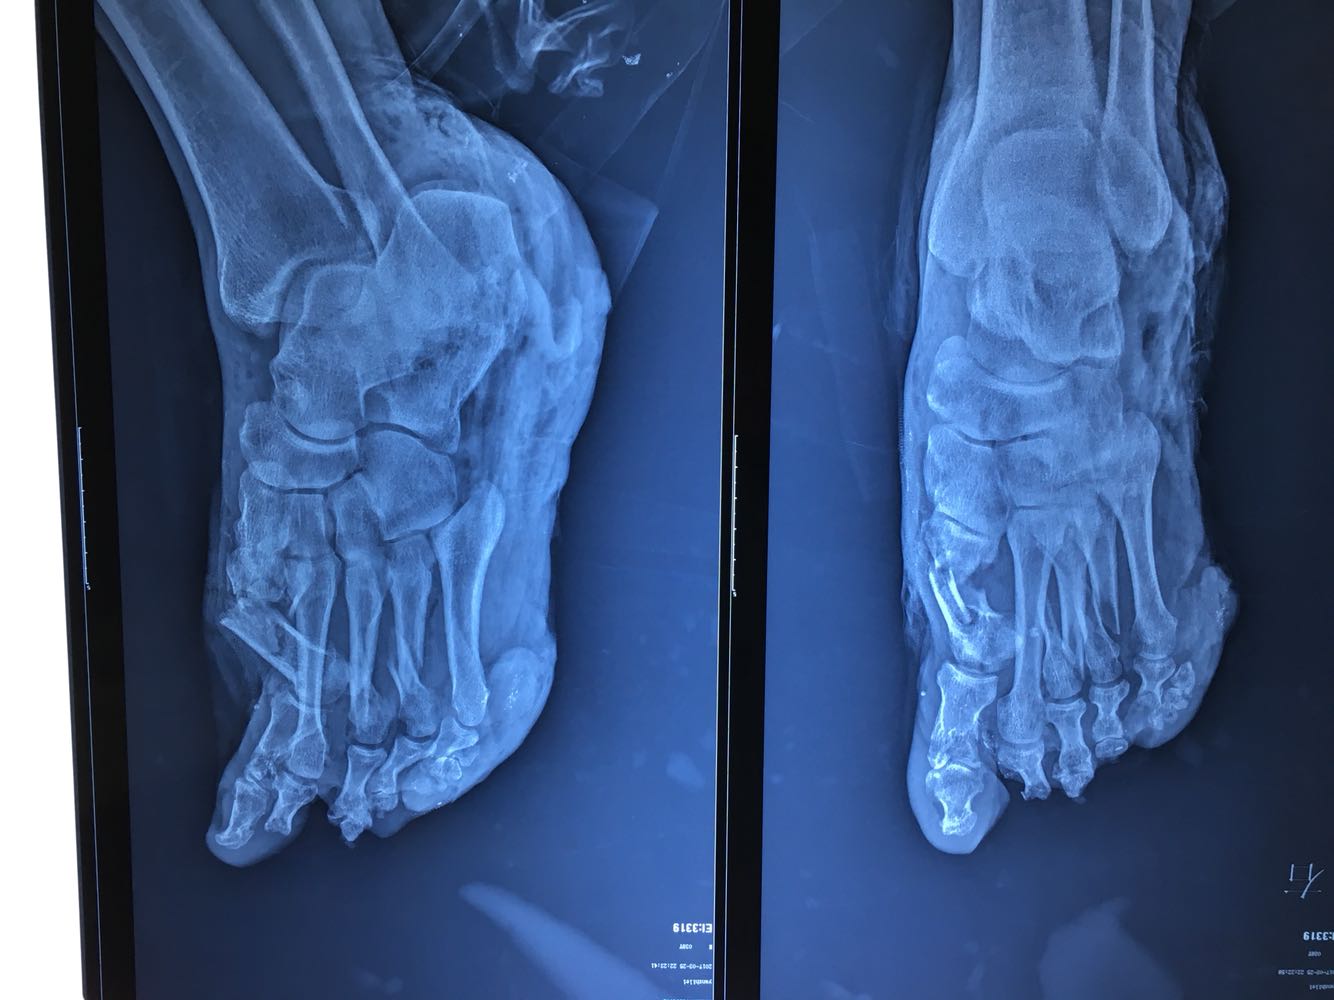

患者男性,38岁,主因双下肢外伤疼痛出血0.5小时来诊。既往病史无特殊。

血压105/60mmHg,心率110次/分,面色苍白,痛苦面容。心肺腹查体无异常。

双下肢开放性骨折 多脏器功能不全 入院后立即给予补液抽血补充血浆及红细胞,完善术前检查,左下肢减张固定,右下肢跖跗关节远端离断。术后患者转至上级医院进一步治疗!